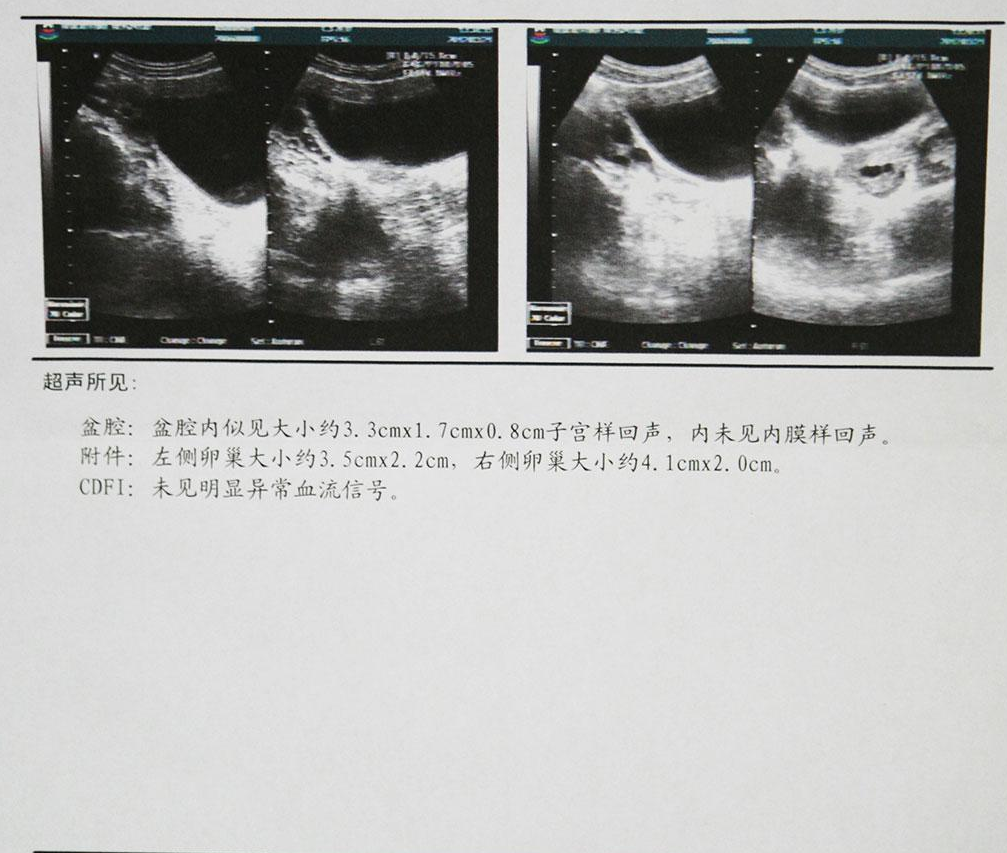

始基子宫,又称痕迹子宫。始基子宫属先天性生殖器发育异常,因两侧副中肾管汇合后不久即停止发育所致,常合并无阴道,但可有正常的输卵管与卵巢。这种子宫极小,仅1~3厘米长,大部分患者无宫腔、无子宫内膜,无月经来潮,且几乎都合并无阴道或仅有2-4cm深的阴道浅窝。阴道四维彩超,可以清晰地看到始基子宫的影像,始基子宫很小,似一条索状,无宫腔。发病率在1/4500,其中无阴道合并始基子宫占80%。肛诊时在相当于子宫颈、子宫体部位,触不到子宫而只扪到腹膜褶。